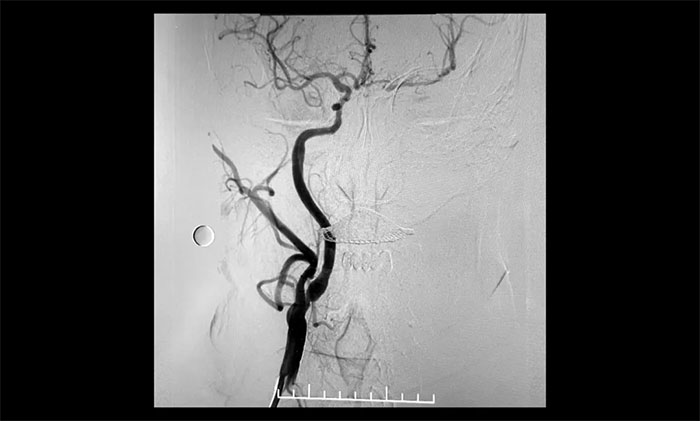

经微导丝成功进入狭窄、闭塞颈内动脉,在支架保护下,进行球囊逐段扩张,支架置入……,经多次球囊扩张,置入支架后,造影显示左颈内动脉起始段狭窄明显改善,左颈内动脉颅内段顺利再通,左颈内动脉眼动脉段、后交通段狭窄明显改善。造影及3D造影见左颈总动脉、左颈内动脉、左大脑中动脉显影可,行支架CT见颅内支架成形可,手术取得成功!

▲术后,左颈内动脉起始段狭窄明显改善,左颈内动脉颅内段顺利再通,左颈内动脉眼动脉段、后交通段狭窄明显改善